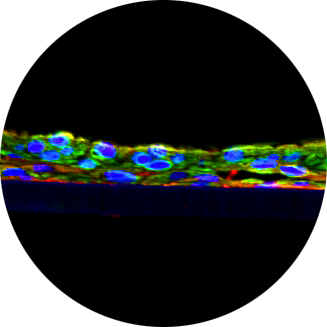

Human Tissue Models

Mattek’s lab-grown human epithelial tissues are living, metabolically active 3D tissue models that provide greater insight into clinical outcomes.